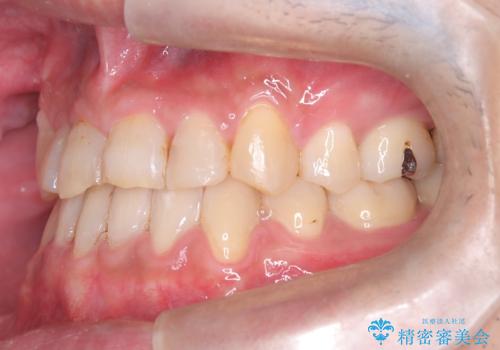

- 主訴:噛み合わせが反対になっているのを治したい

反対咬合と叢生改善のため、上下左右4番目の歯を抜歯し、審美装置にて矯正治療を行いました。

骨格性Ⅲ級を示しましたが、構成咬合位がとれたことから反対咬合と叢生改善のため、上下左右第一小臼歯を抜歯しワイヤー矯正を行いました。途中、バイトアップを行っています。